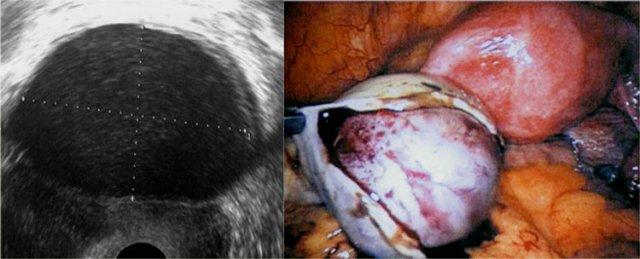

Trên siêu âm đầu dò âm đạo, nang lạc nội mạc tử cung có thể được nhận thấy là các nang thành dày với các hồi âm mức độ thấp.

Bên trái là hình ảnh siêu âm đầu dò âm đạo và hình ảnh nội soi ổ bụng tương ứng trong quá trình cắt nang.

Trên MRI, nang lạc nội mạc tử cung biểu hiện là các khối đơn độc hoặc đa ổ với tín hiệu tăng đồng nhất trên chuỗi xung T1 và T1 xóa mỡ.

Chuỗi xung T1 xóa mỡ giúp phân biệt nang lạc nội mạc tử cung với u quái dạng nang trưởng thành, thường chứa mỡ.

Trên chuỗi xung T2W, nang lạc nội mạc tử cung có thể có tín hiệu từ giảm tín hiệu (còn gọi là hiệu ứng shading) đến tín hiệu trung gian hoặc tăng tín hiệu.

Tín hiệu thấp phản ánh tình trạng cô đặc máu trong nang.

Nang lạc nội mạc tử cung thường có vỏ xơ dày với giảm tín hiệu trên T2, do các đại thực bào chứa hemosiderin gây ra (hình minh họa).